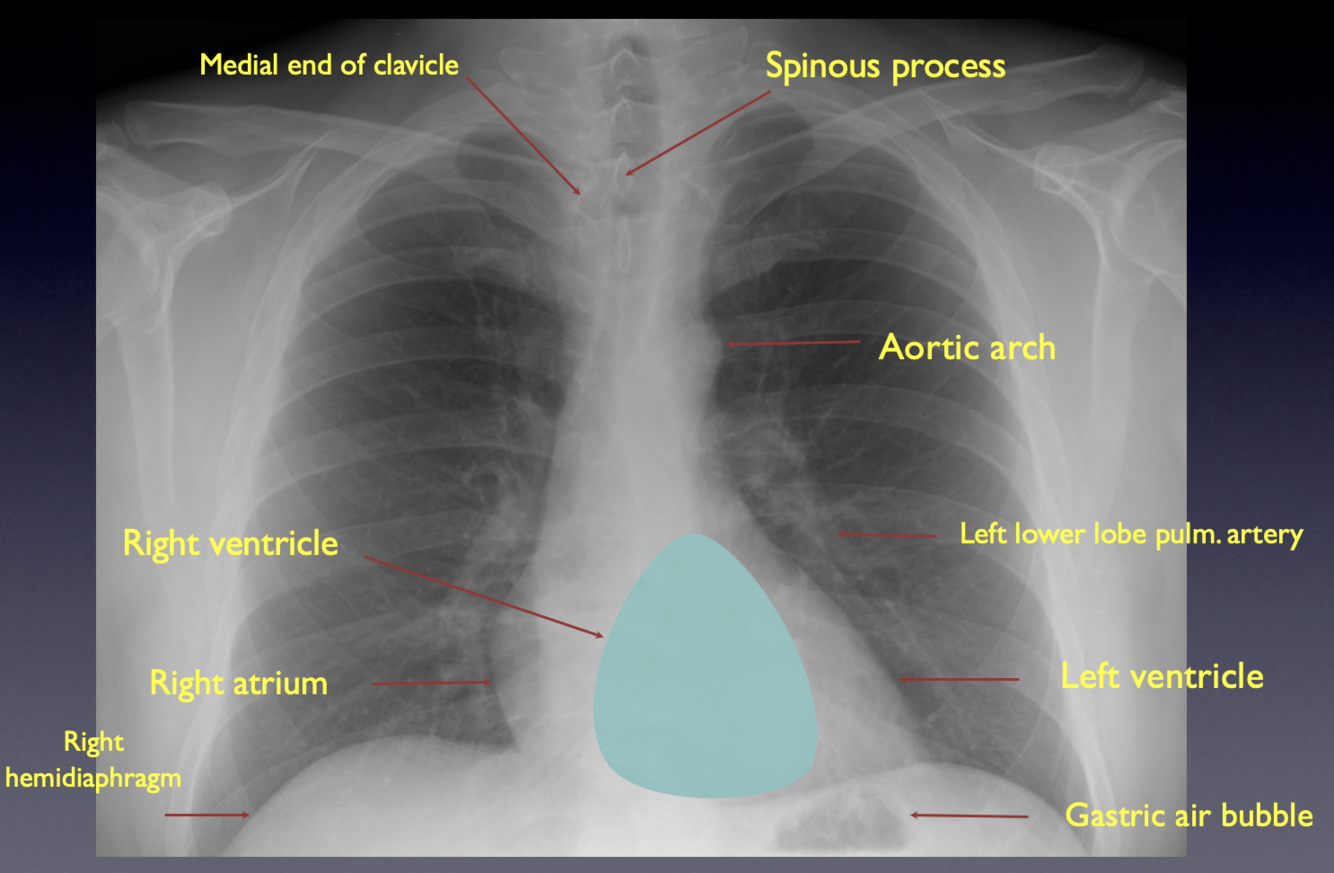

How can a properly rotated CXR be identified ?

A

If a CXR is correctly centred, the medial ends of the clavicles should be equidistant from the spinous processes of the upper thoracic vertebrae

-Poorly inspired can simulate pathology when there is none